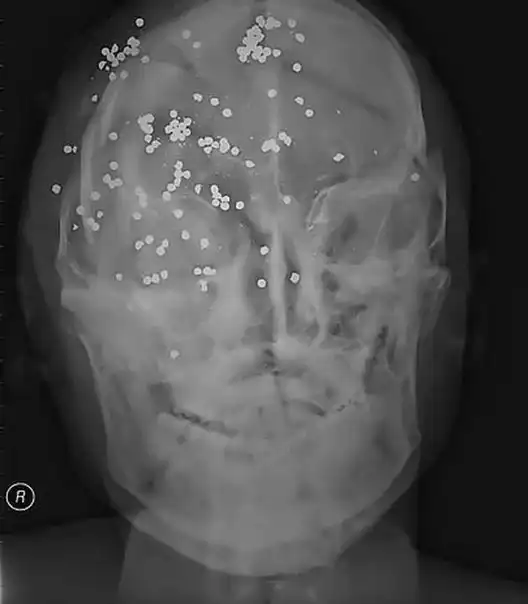

Ранения дробью в голову.